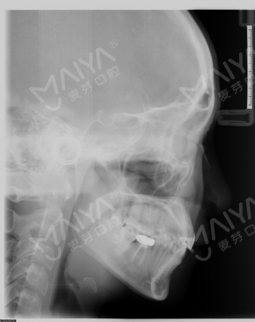

经朋友介绍来矫正,医生说了一堆安慰我年龄不是问题,服务态度好好哦~另外说牙齿非常不整齐,右下有个磨牙缺失不能种,为了我的工作考虑,采取了隐形正畸技术,拔了智齿,然后排齐牙齿,上图,这就是露牙后的效果,总感觉哪里怪怪的~~